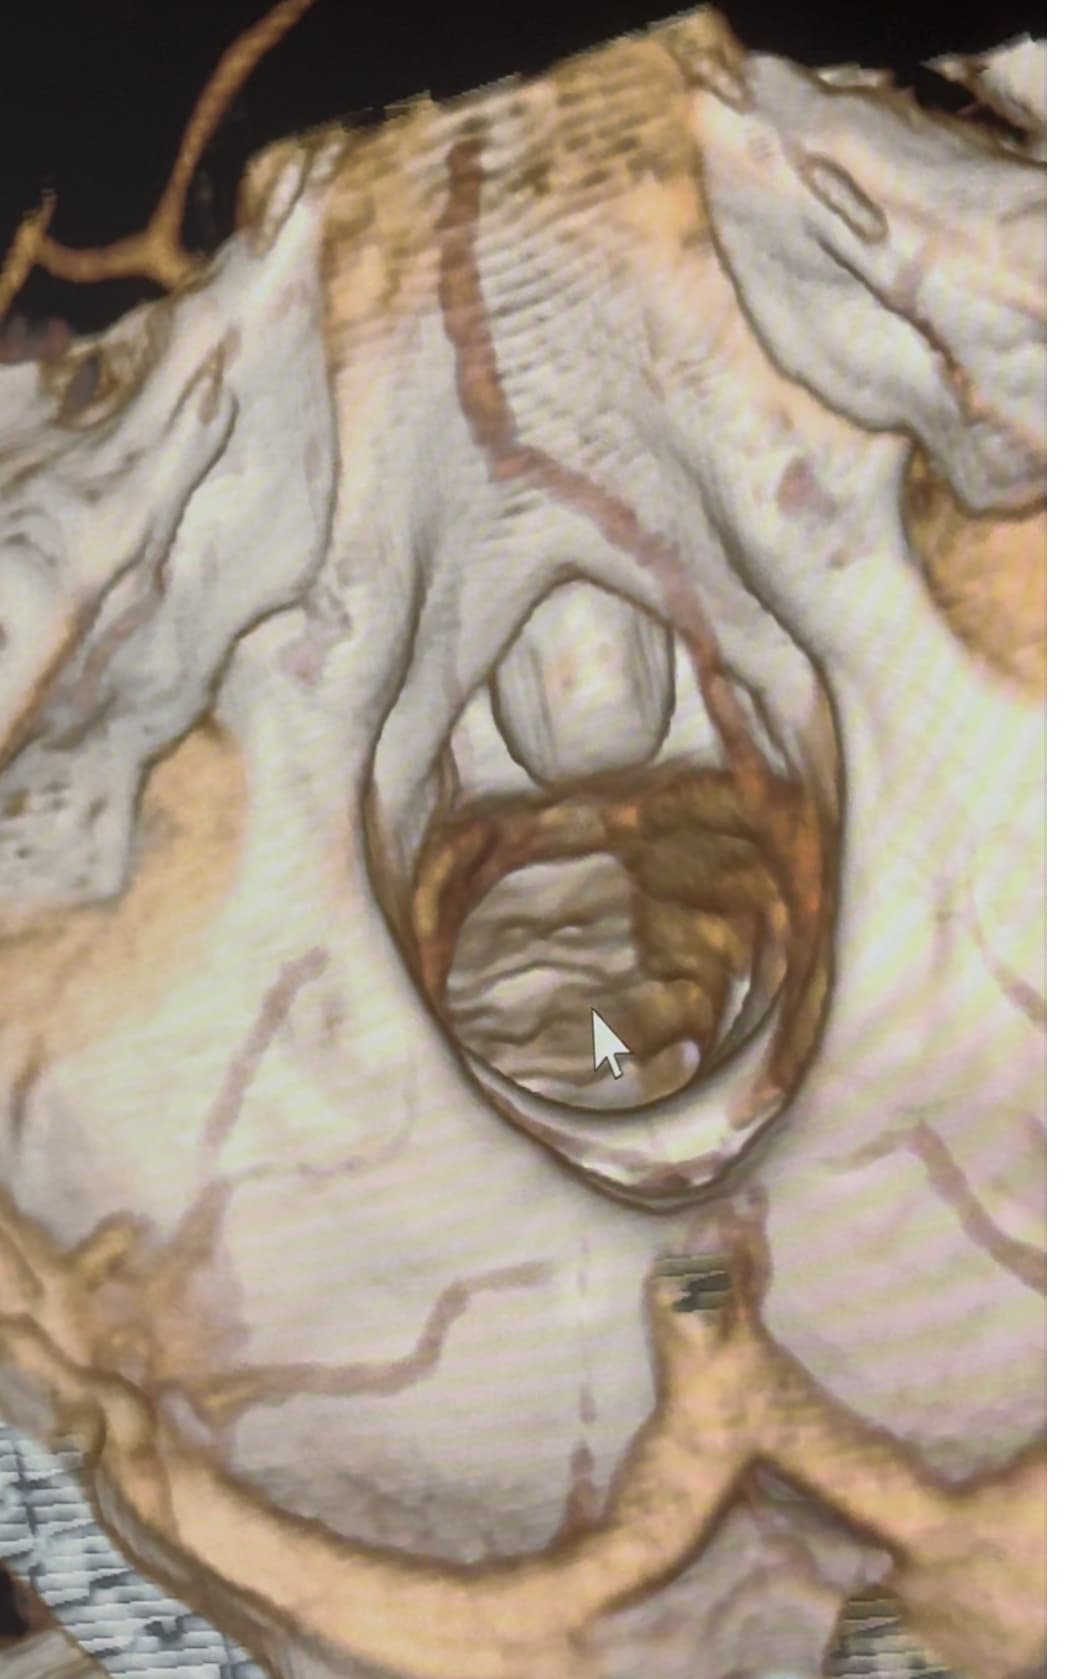

@Rob12345 I can help you get a better look at the IJV compression at the level of C1.

If you go into your original CT imaging, go to the axial view. Then scroll to C1. I’ve attached my own imaging to help you know what to look for.

@Rob12345 can you go into the axial view of the original imaging and go to C1? It’s the best view for showing IJV compression by C1 and styloids. I’ve attached my own imaging to help you find C1 in the axial view.

@Rob12345 - I can see you have bilateral IJV compression in the images you’ve posted & it’s possible the middle image in your first set of pictures is pointing to collateral veins. I’m not great at identifying collaterals, but I can say for sure your IJVs are being squashed between your styloids & C1.